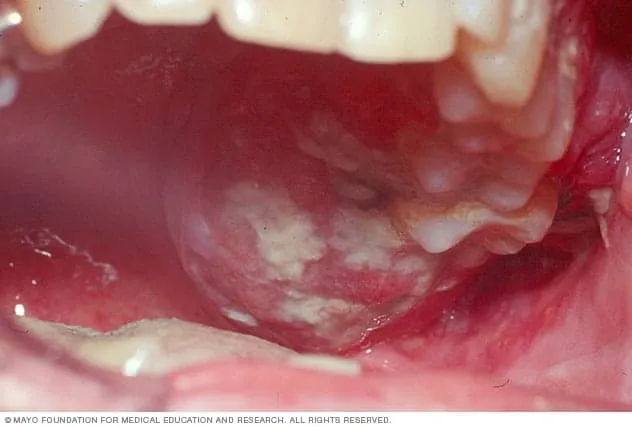

Hãy thử so sánh biểu hiện của bạn với những hình ảnh ung thư khoang miệng sau đây:

Mảng trắng ung thư